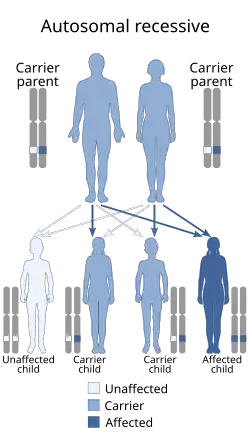

Genetics

PYCD is a rare autosomal recessive disorder.[12][13] The molecular basis of pycnodysostosis was elucidated in 1996 by Gelb and collaborators and the disorder results from biallelic pathogenic mutation in CTSK gene (OMIM * 601105). This gene codes for cathepsin K, a lysosomal cysteine protease that is highly expressed in osteoclasts and plays a significant role in bone remodelling by degenerating the bone matrix proteins such as type I collagen, osteopontin, and osteonectin. Defective function of cathepsin K therefore results in failure of normal degradation of the accumulated collagen fibres in the resorptive microenvironment by osteoclasts despite normal generation of ruffled membranes and mobilization of bone minerals.

If both parents of a diagnosed individual are heterozygous for a CTSK pathogenic variant, siblings of the individual have a 25% chance of being affected, a 50% chance of being an asymptomatic carrier, and a 25% chance of being unaffected and not a carrier.[14]